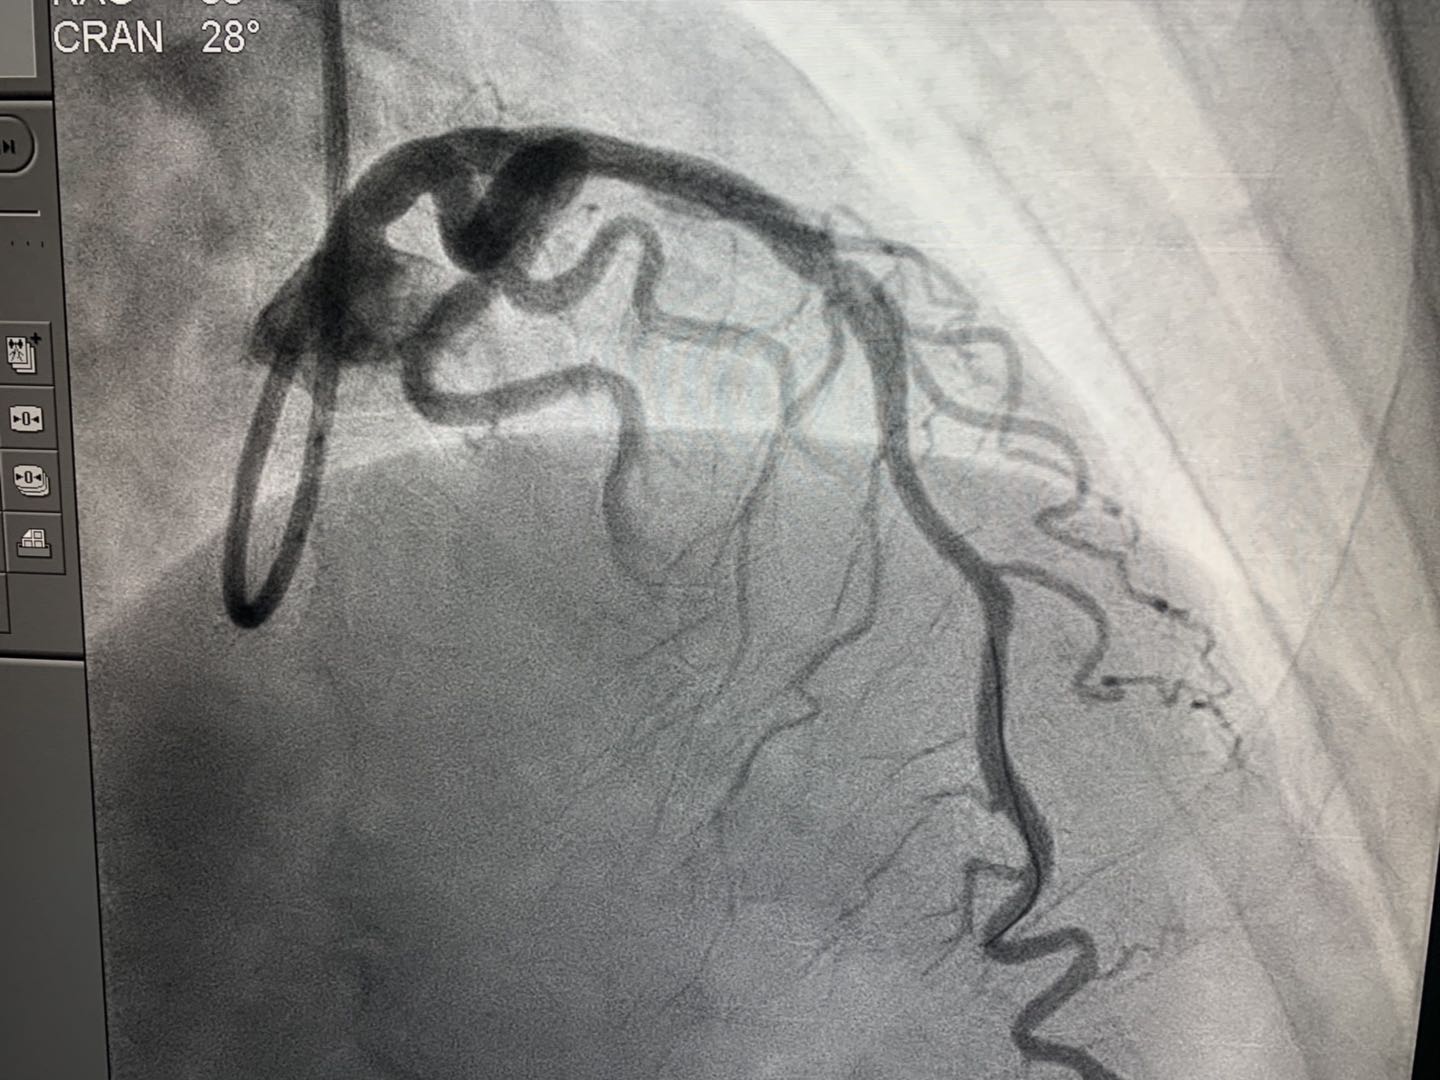

2019年4月16日,新疆首例生物可吸收心脏支架植入术在beat365中文官方网站附属中医医院(自治区中医医院)成功实施。医院心脏中心冠脉介入团队在武刚主任带领下,为一例50岁男性患者冠状动脉前降支近端成功植入NeoVas生物可吸收支架一枚。术中、术后采用光学相干断层扫描(OCT)对冠脉病变及植入支架进行评估。手术顺利,患者体征平稳。

NeoVas支架,全称为“生物可吸收冠状动脉雷帕霉素洗脱支架系统”,其基体及药物载药涂层分别由可吸收材料制成,支架基体和涂层在体内逐步生物降解和吸收,无永久性支架存患者体内。简单讲,传统支架是金属制成的,一旦进入人体将永久存在,此次使用的可吸收支架是由可降解材料制成,进入人体后会逐渐溶解并消失,不会在体内留下异物,避免了患者受到血管二次堵塞风险。

心内二科武刚主任介绍,心脏支架是心脏介入手术中最常用的医疗器械,具有疏通动脉血管的作用。由于这个“外来物”一旦进入人体后就要终身携带,这也让一些患者特别是年轻的心脏病人产生担忧。冠心病介入治疗(PCI)已经经历了三代技术发展:单纯球囊扩张术、金属裸支架(BMS)和药物洗脱支架(DES)。生物可吸收支架是冠脉支架的发展方向,可解决药物洗脱金属支架永久异物的痛点。目前世界范围内应用的支架大部分是第三代支架——药物洗脱支架,由于其材质为金属的,植入后会在人体内永久存留金属异物。

武刚主任医疗团队此次植入可吸收支架的材料为聚乳酸等,在植入体内后2-3年可完全降解,而且可以恢复血管的功能和弹性,不会永久存留,所以被认为是冠心病治疗的第四次革命。同时对于金属支架过敏的冠心病患者是个很好的选择。预计未来可吸收支架会被广泛使用,冠心病介入治疗将进入新的时代。(介入治疗室魏玲)